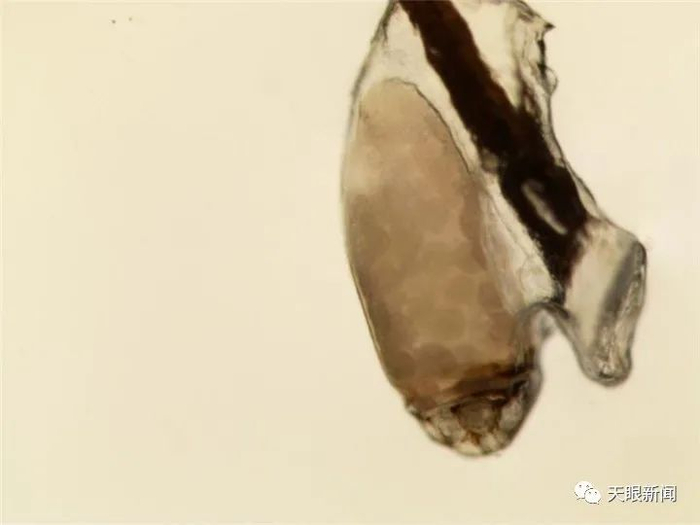

李英琦有些不敢相信自己的眼睛,显微镜下,晓晓右眼的每根睫毛都挂着一串琥珀色的虫卵,还有三只体长2毫米左右的成虫用钳子紧紧攀附于睫毛根部。

显微镜下的虱子

国果教授表示,虱子分类很多,常见的就有头虱、体虱、阴虱三种,通过比对可知,寄生在孩子睫毛上的是“阴虱”。阴虱有钩型巨爪,胸腹相连处无明显分界,腹部宽短,略似螃蟹。常以其巨爪紧握住毛发,也可爬伏在皮肤上,看起来似一淡黄色或灰色斑点,大小为1.5-2毫米。